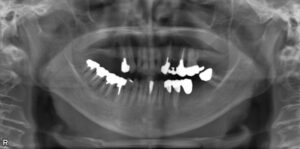

上下臼歯5本欠損症例

BEFORE AFTER 74歳女性/上下5本欠損/インプラント埋込手術 【治療内容】 右上第二小臼歯、第一、第二大臼歯…